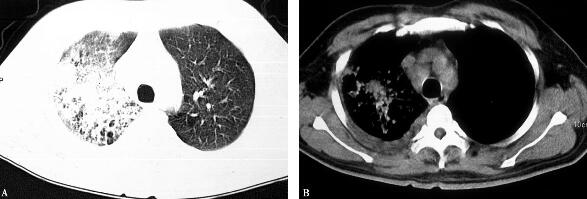

5.胸部CT(治疗5天后):肺部阴影进行性发展(图2)。

图2

结合病史、查体、实验室及影像学检查,均支持CAP的诊断。但是经过积极的抗感染治疗,该患者临床症状好转不明显,血生化检查虽有所下降,但仍明显高于正常值,复查胸部CT呈进行性发展,且患者先后出现消化系统及神经系统症状,综合分析上述临床资料可以用一种疾病解释—军团菌肺炎。